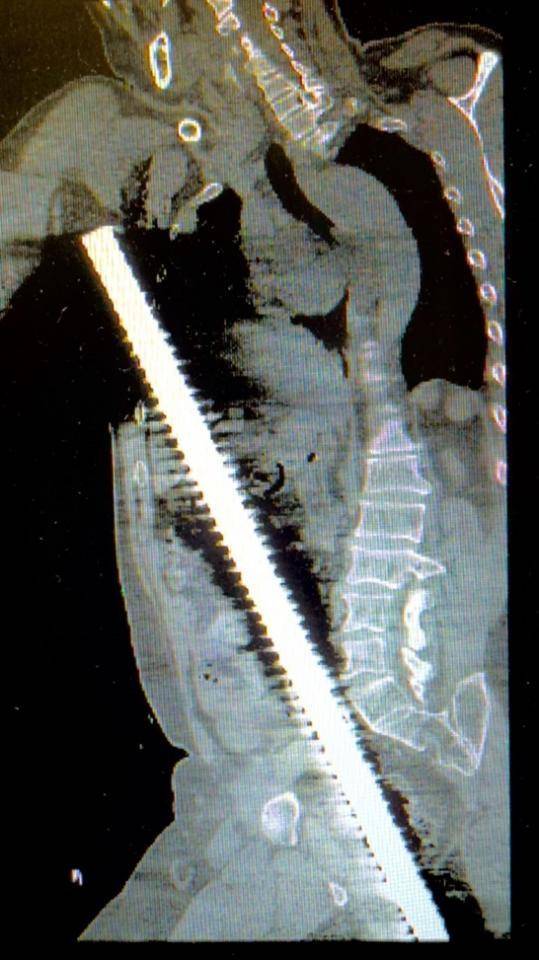

急诊医生接诊后,只见患者臀部附近露出一根长约15厘米,直径约3公分的钢筋。当即启动创伤应急机制,迅速开通静脉通路、实施心电监护、快速补液稳定血压,伤者被快速送至急诊中心CT室进行全身扫描。影像显示,钢筋已贯穿盆腔、腹腔至胸腔,伤情凶险至极。急诊中心同步为患者实施深静脉穿刺置管,为输血、输液建立大流量通道。此时,医疗、护理、行政、院领导四大总值班接到汇报,迅速组织普外科、心胸外科、泌尿外科、创伤外科、ICU等科室进行多学科MDT紧急会诊。

CT 2D、3D重建显示钢筋穿透盆腔、腹腔、胸腔

夜深人静的手术室灯火通明,监护仪的滴滴声、呼吸机的呼啦声显得格外清晰。"钢筋的位置靠近腹部大血管和肝门部,钢筋可能暂时压住出血点,如果贸然将钢筋拔除,可能导致灾难性大出血。"参加抢救的医生低声讨论着手术要点,大家个个神经紧绷、沉着应对。手术团队是嵇振岭教授、刘宗航副主任、强光辉副主任、以及于宽勇主治医生,台上台下,井然有序,配合默契。探查发现这根近3公分粗的螺纹钢筋从会阴部刺入,经过盆腔穿透乙状结肠,紧贴腹部主动脉右侧挤压下腔静脉和髂血管,从后腹膜处穿过小肠系膜,横结肠系膜直达肝门右侧,在胆囊右侧进入肝脏,从肝脏膈面穿出,再穿透膈肌进入胸腔,直达右侧腋下。

患者伤情明确:会阴部盆腔穿透伤、乙状结肠穿透伤、小肠系膜穿透伤、横结肠系膜穿透伤、肝脏穿透伤、膈肌穿透伤、胸廓穿透伤等多重致命损伤。